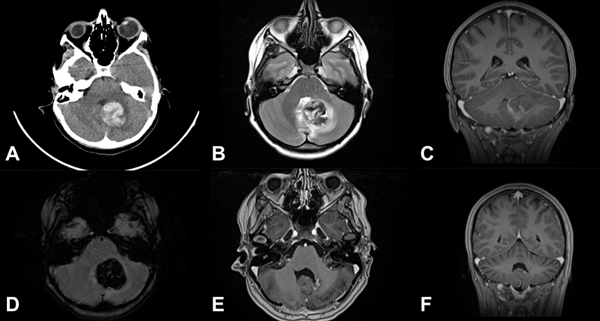

Figura 2. Cavernoma cerebral supratentorial profundo, ubicado en la cabeza del núcleo caudado izquierdo. Paciente femenina de 10 años que ingresa por síndrome de hipertensión endocraneana y primer episodio de sangrado con volcado intraventricular A) requiriendo colocación de drenaje ventricular externo. Evolucionó favorablemente. B) RM cerebral secuencia T2, paciente reingresa a los 2 meses por nuevo sangrado, agregando hemiparesia crural derecha, se decide cirugía programada. C) RM secuencia DTI-tractografía, realizada para planificación quirúrgica. D) RM cerebral, planificación quirúrgica mediante neuronavegación, eligiendo un abordaje transcalloso contralateral. E) y F) RM secuencias T2 y T1 en el postoperatorio, muestran la resección completa. G) y H) Imágenes microquirúrgicas. Se observa la hoz del cerebro y el cavernoma disecado (flecha blanca), en la línea de puntos blanca se observa el lecho quirúrgico con restos de hemosiderina.

Figura 3. MC cerebral infratentorial del tronco del encéfalo. Paciente masculino de 5 años que ingresa por síndrome cerebeloso, asociado a hemiparesia faciobraquiocrural izquierda. Evoluciona favorablemente, egreso hospitalario. A los 2 meses reingresa por un episodio de resangrado. Se decide cirugía programada. A) RM T2 FIESTA que muestra lesión protuberancial, heterogénea, con halo hipointenso. B) RM T1 con contraste EV que muestra sangrado en distintos estadios. C) RM SWI imagen típica. D) y H) RM DTI-tractografía que muestra tractos pontinos transversos en rojo y pedúnculo cerebeloso medio en verde, en este caso se eligió un abordaje supracerebeloso infratentorial lateral y se accedió al cavernoma a través del surco mesencefálico lateral. E-G) RM postquirúrgica de cerebro secuencia T1 en los 3 planos, se evidencia la resección completa de la lesión.

Figura 4. Cavernoma del tronco del encéfalo. Paciente masculino de 11 años, antecedentes de cirugía de resección parcial del cavernoma en dos oportunidades e hidrocefalia que requirió sistema de derivación ventriculoperitoneal. Ingresó por déficit neurológico focal progresivo que agregó trastornos deglutorios, episodios de apneas y paro cardiorrespiratorio, por lo que se realizó la revisión valvular, sin mejoría, para luego efectuar cirugía de resección del cavernoma. Resección completa. Paciente evoluciona favorablemente recuperando función respiratoria y parcial del déficit motor. A) TC de cerebro de urgencia sin contraste que muestra sangrado bulboprotuberancial extenso. B) RM postoperatoria de cerebro con contraste EV, corte coronal, lecho quirúrgico libre de lesión. C) Corte sagital del mismo estudio, nótese el trayecto de disección, generando imagen de tronco “atravesado”.

Figura 5. MC cerebral infratentorial cerebelosa. Paciente femenino de 15 años, consulta por síndrome cerebeloso. A) TC de cerebro que muestra imagen espontáneamente hiperdensa en región vermiana y pedúnculo cerebeloso medio izquierdo. B) RM secuencia T2 que muestra lesión heterogénea con edema perilesional. C) RM secuencia T1 con contraste EV en plano coronal que muestra la relación de la MC con el receso superolateral. D) RM-SWI que muestra lesión con componentes hemáticos. E-F) RM postquirúrgica cerebral, secuencia T1 con contraste EV, se muestra resección completa de la malformación cavernosa.

Figura 6. MC medular a nivel T10. Paciente masculino de 15 años que ingresa por paraplejía progresiva de varios días de evolución y compromiso de esfínteres. A) RM de columna dorsolumbar corte sagital T2-STIR que evidencia lesión heterogénea, compatible con MC. B) RM corte axial T2-STIR. C-D) RM de cerebro secuencias SWI y T2 que muestra otra lesión en hemisferio cerebeloso derecho. Por la severidad del cuadro clínico se realizó cirugía de urgencia. E-F) RM de columna dorsolumbar postquirúrgica, secuencias T1 y T2-STIR donde se observa el lecho quirúrgico libre de lesión. Se observa laminectomía del nivel T10. El paciente tuvo una recuperación parcial del foco neurológico. Actualmente en rehabilitación.

Figura 7. SMCCF. Paciente masculino de 12 meses que ingresa por cuadro de estatus convulsivo. Ingresa a cirugía de urgencia para resección de lesión temporal. Por persistir con crisis se realiza reexploración y exéresis de lesión frontal, tras lo cual controla las adecuadamente. A-C) TC cerebral con contraste EV que muestra dos lesiones hemorrágicas extensas en distintos estadios. Lesión temporal derecha subaguda, frontal derecha quística en reabsorción. D) y E) RM de cerebro secuencia SWI que pone de manifiesto múltiples lesiones, efecto “blooming” de distintos tamaños corticosubcorticales y profundas. F) Lesiones negativas en la secuencia T2.